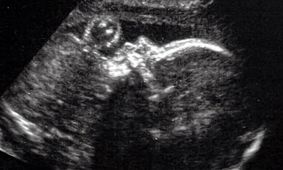

جراحی مغز جنین پیش از تولد در آمریکااقتصاد ۱۰۰ - جراحان با انجام این عمل موفق، توانستهاند تا یکی از ناهنجاریهای مغزی پیش از تولد را درمان کنند.